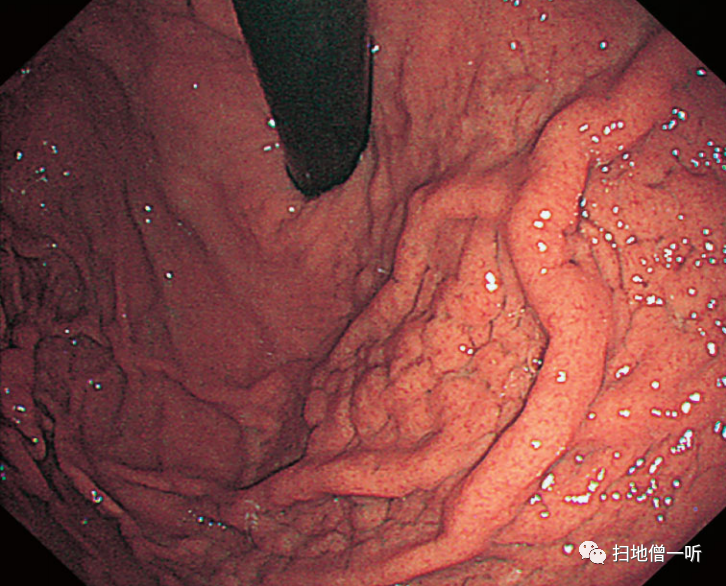

【胃底腺息肉】

患者70多岁,女性。呈水肿样外观的胃底腺息肉。

▲病理组织学上,主要由壁细胞构成的胃底腺囊胞状扩张以及壁细胞障碍。

胃底腺息肉是H.pylori阴性者的观察结果,国外的横向研究和队列研究表明,长期服用PPI者的胃底腺息肉增加。而且,在日本的队列研究中,表明了H.pylori阴性者的特征是使用PPI引起的胃底腺息肉增大。PPI中增大的胃底腺息肉的内镜特征是显示出水肿样膨化的多房样形态。在病理组织学上,主要由壁细胞组成的胃底腺有明显的囊胞状扩张所见,伴有类似PCP的壁细胞障碍。